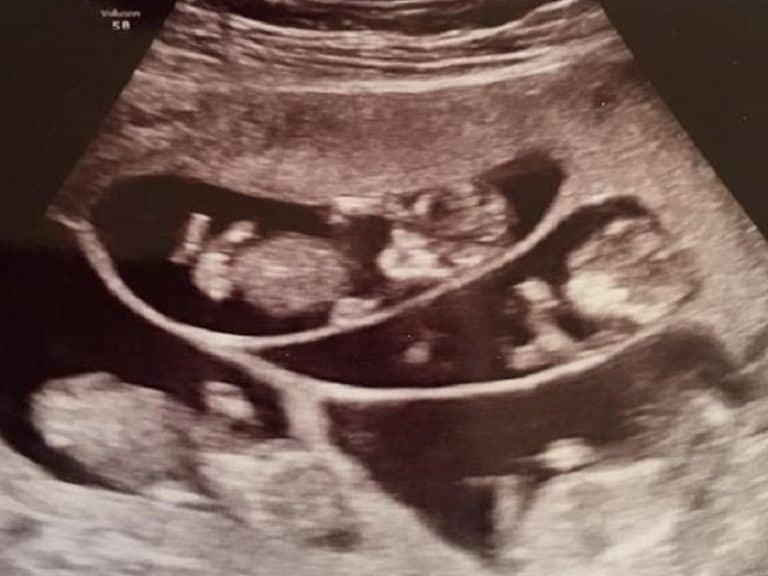

Μια απίστευτη έκπληξη κατά διάρκεια ενός απλού ελέγχου

Κάνοντας οι γονείς το πρώτο τους υπερηχογράφημα θεώρησαν πως θα είναι μια απλή εξέταση από τον γιατρό. Όμως ο υπέρηχος έδειξε ένα, δύο, τρία… συνολικά επτά έμβρυα! Η ανατροφή ενός παιδιού είναι πάντα υπεύθυνο ζήτημα, πόσο μάλλον επτά παιδιών. Αλλά και ο κίνδυνος για την Bobbi ήταν μεγάλος, καθώς θα έπρεπε να μεγαλώσει επτά παιδιά στην κοιλιά της. Είχε τώρα να τα βγάλει πέρα τόσο με τις δυσκολίες της εγκυμοσύνης, όσο και με τα συναισθήματα της, από την μία την ευτυχία και από την άλλη το φόβο. Και ήταν ακόμα στην αρχή.